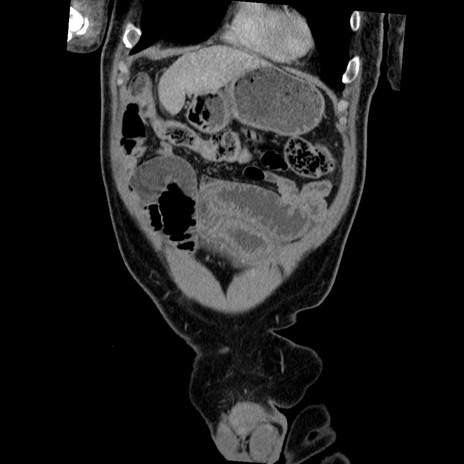

横断像

【症例】50歳代男性

【主訴】腹痛

【現病歴】AVMからの被殻出血のため回復期リハ病棟入院中。 本日午後3時頃急に下腹部痛が出現した。

【既往歴】AVM、被殻出血、虫垂炎、高血圧

【身体所見】意識晴明、左半身不全麻痺、会話の理解は良好、36.5°C、腹部:膨隆、全体に板状硬、下腹部正中に圧痛点あり、反跳痛-、筋性防御不明、右下腹部にope scar

【データ】WBC 9400、CRP 0.06